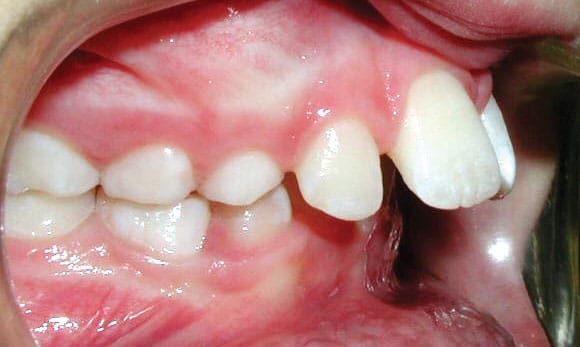

Crossbite

The upper teeth sit inside the lower teeth, which may cause misaligned jaw growth.